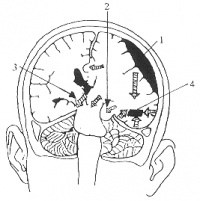

脑动脉闭塞导致多发性梗死和脑组织容积减少

颈内动脉或大脑中动脉起始部反复多次的发生动脉粥样硬化性狭窄及闭塞,使大脑半球出现多发性的较大

的梗死病灶,或出现额叶和颞叶的分水岭梗死,使脑组织容积明显减少,当梗死病灶的体积超过80~100ml 时,可因严重的神经元缺失和脑萎缩出现认知功能障碍的临床表现。

出血性病变

包括脑组织外出血的硬膜下血肿和蛛网膜下腔出血,以及大脑半球内出血性血肿,对脑实质产生直接破坏和间接压迫,并阻塞了脑脊液循环通路,临床逐渐出现不同程度的痴呆表现。

MID定义为大血管阻塞所导致的大面积梗死,尤其是多发生在内环状动脉或Willis环及其它主要大脑动脉上。

关键性梗死性痴呆

关键性梗死性痴呆是由重要皮质、皮质下功能区域的几个小面积梗死灶,有时甚至是单个梗死病灶所引起。最为人们所知的是双侧丘脑梗死导致的具额叶特征的痴呆,其它关键部位如角回、基底前脑-基底下丘脑结构、带状回的病灶也可导致痴呆。